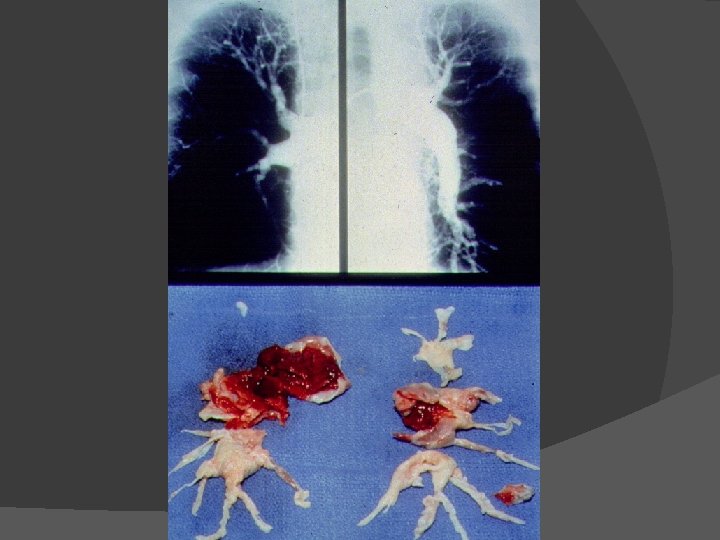

Angiografia pulmonar

Conventional pulmonary angiogram of the right lung with intraluminal filling defects in the lobar artery and segmental and subsegmental arteries of the lower lobe. Kearon C CMAJ 2003; 168: 183 -194 © 2003 by Canadian Medical Association

Kearon C CMAJ 2003; 168: 183 -194 © 2003 by Canadian Medical Association